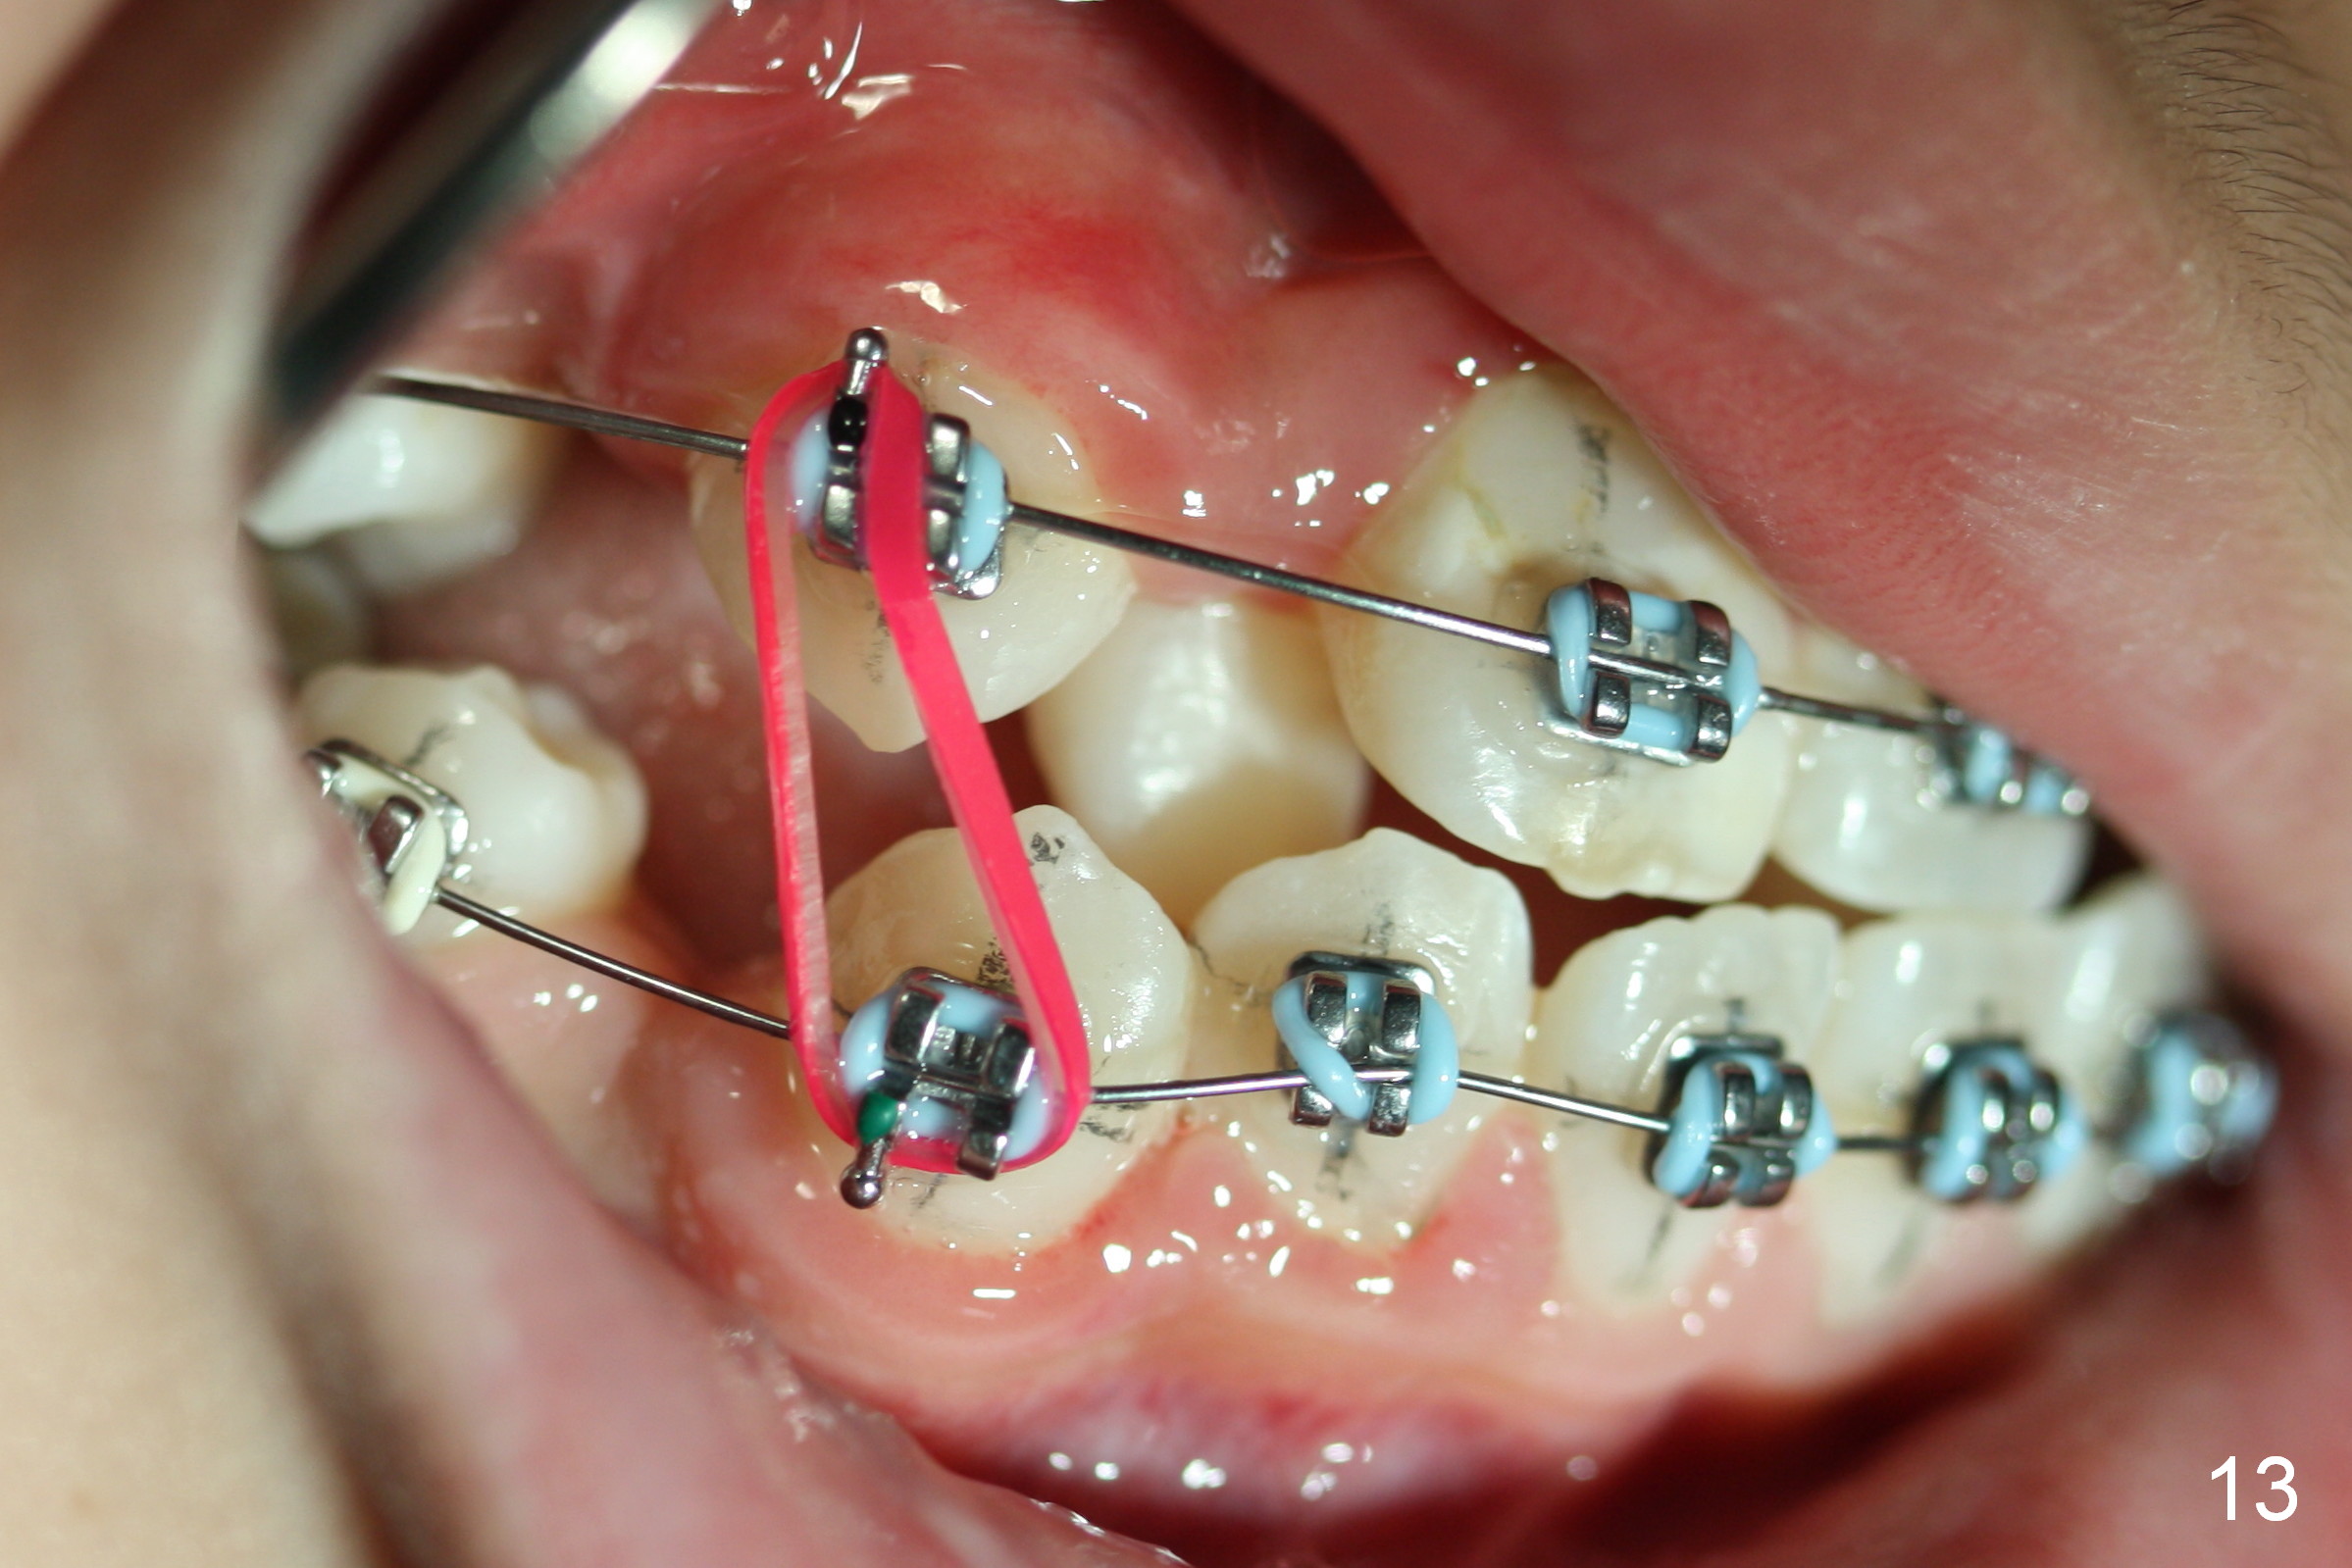

One month post banding, the upper wire changes to .016', while the lower one remains .014' with LR2 bracket partially engaged (Fig.13). Intuitively, an elastic is placed between UR3 and LR3. It appears that these two teeth have been moved occlusally and distally quite a bit in 1 month.